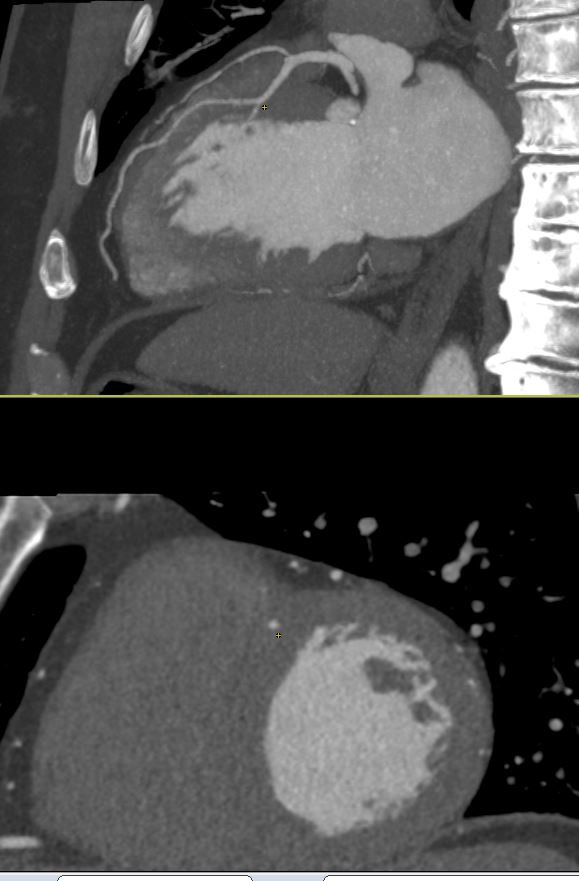

Reading #YesCCT I have seen many intramuscular LAD but this one struck me as particularly deep in the myocardium and long (44mm) in a chest pain pt #MorristownCards @Heart_SCCT @mmartinezheart @LindaGillamMD @CardiacConsult @lillian_aldaia @PhilGenereuxMD